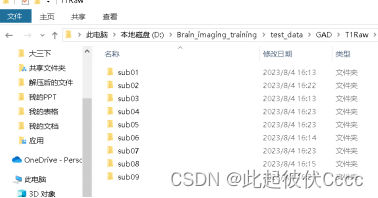

(1) 将工作路径切换至图像数据存在的地方,并在该路径下按如下图格式创建文件夹,其中T1Img文件夹中存放未经过格式转换的被试.dcm文件。

每个subxx文件存放被试的.dcm图像文件: